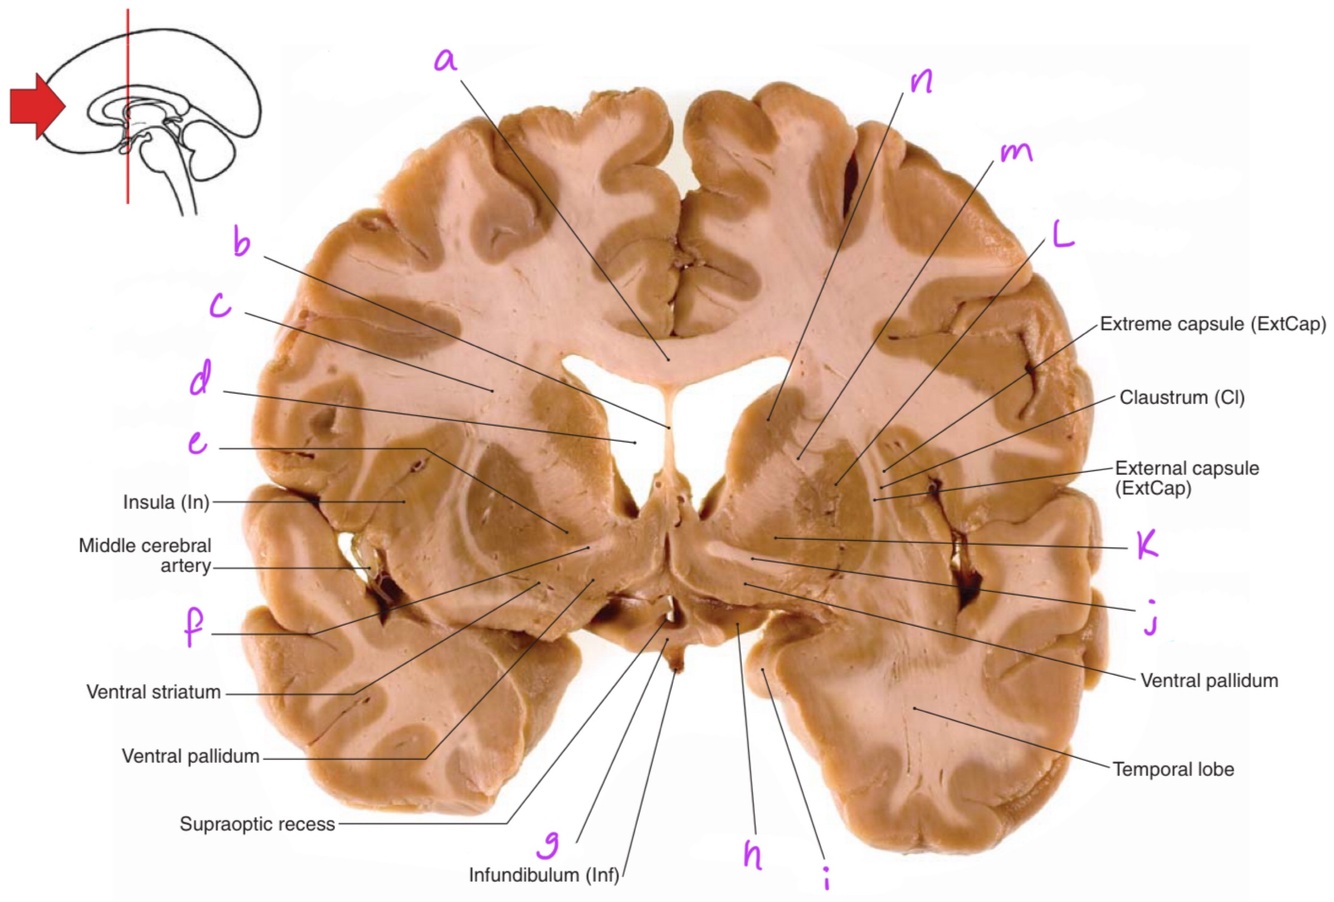

a

body of corpus callosum

b

Anterior horn of lateral ventricle

c

Septum pellucidum

e

Q

g

Putamen

Corona radiata

Globus pallidus

f

Anterior commissure

Optic chiasm

Optic tract

Uncus

Anterior limb of internal capsule

Head of caudate nucleus